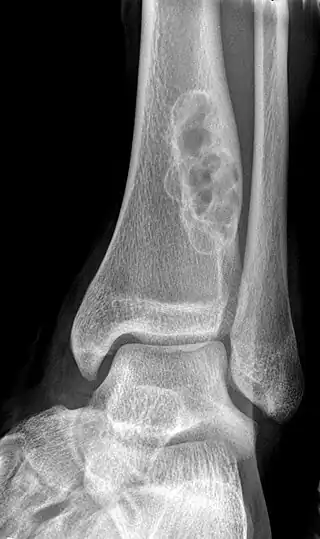

| X-ray of nonossifying fibroma of distal tibia. | |

Diagnosis is by X-ray or MRI, usually when investigating a person for something else.[3] Medical imaging typically shows a well marginated radiolucent lesion, with a distinct multilocular appearance, sometimes looking like bubbles.[3] It is usually around 1-2cm in size, but be as large as 7cm.[4] They consist of foci consist of collagen rich connective tissue, fibroblasts, histiocytes and osteoclasts.[3] Usually no treatment is required.[4] Surgical curettage and bone grafting may be required if it is large.[4]

It is usually iagnosed by x-ray or MRI, when investigating another problem.[1] The tumor presents as a well defined radiolucent lesion, with a distinct multilocular appearance, sometimes looking like a "soap bubble".[2] If small and no symptoms, then biopsy is not needed.[1]